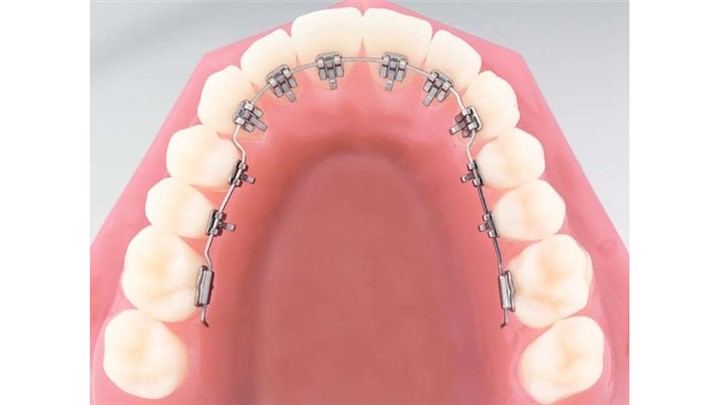

ارتودنسی لینگوال

ارتودنسی لینگوال یا پشت دندانی نیز نوع دیگری از ارتودنسی ثابت است که ارتودنسی کاملا نامرئی است؛ زیرا در این روش ارتودنسی فلزی به جای جلوی دندان ها به پشت دندان ها چسبیده می شود و از نظر اطرافیان پنهان است.

مزایای ارتودنسی لینگوال

- کاملا نامرئی است.

معایب ارتودنسی لینگوال

- هزینه بسیار بالا به دلیل سخت بودن نصب آنها توسط پزشک

- اختلال در تکلم

- سخت تر شدن رعایت بهداشت دهان و دندان